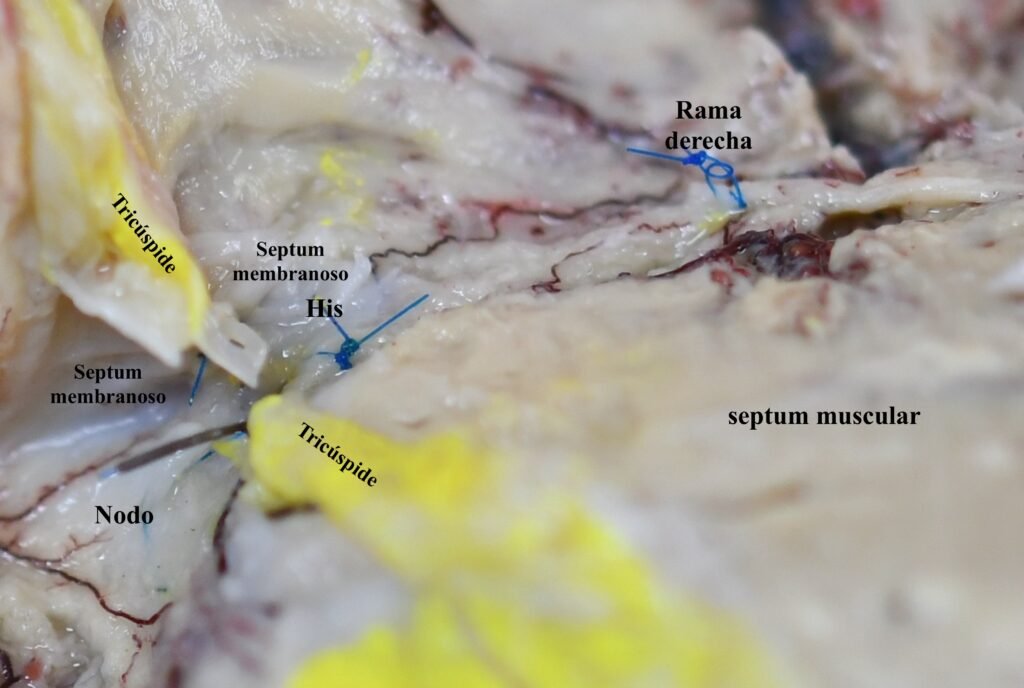

Se ha “coloreado” con técnica digital el sistema de conducción para su didáctica visualización. Recomendamos observar esta fotografía y las previas para mejor orientación.

El Nodo, fascículo y rama derecha del sistema de conducción se visualizan transcurriendo por el atrio derecho, a caballo de el septum muscular e inmediatamente por debajo de la porción membranosa del septum. Las referencias de las fuentes vasculares se han minimizado a efectos de que la identificación sea personal y corroborada mediante las fotografías previas.